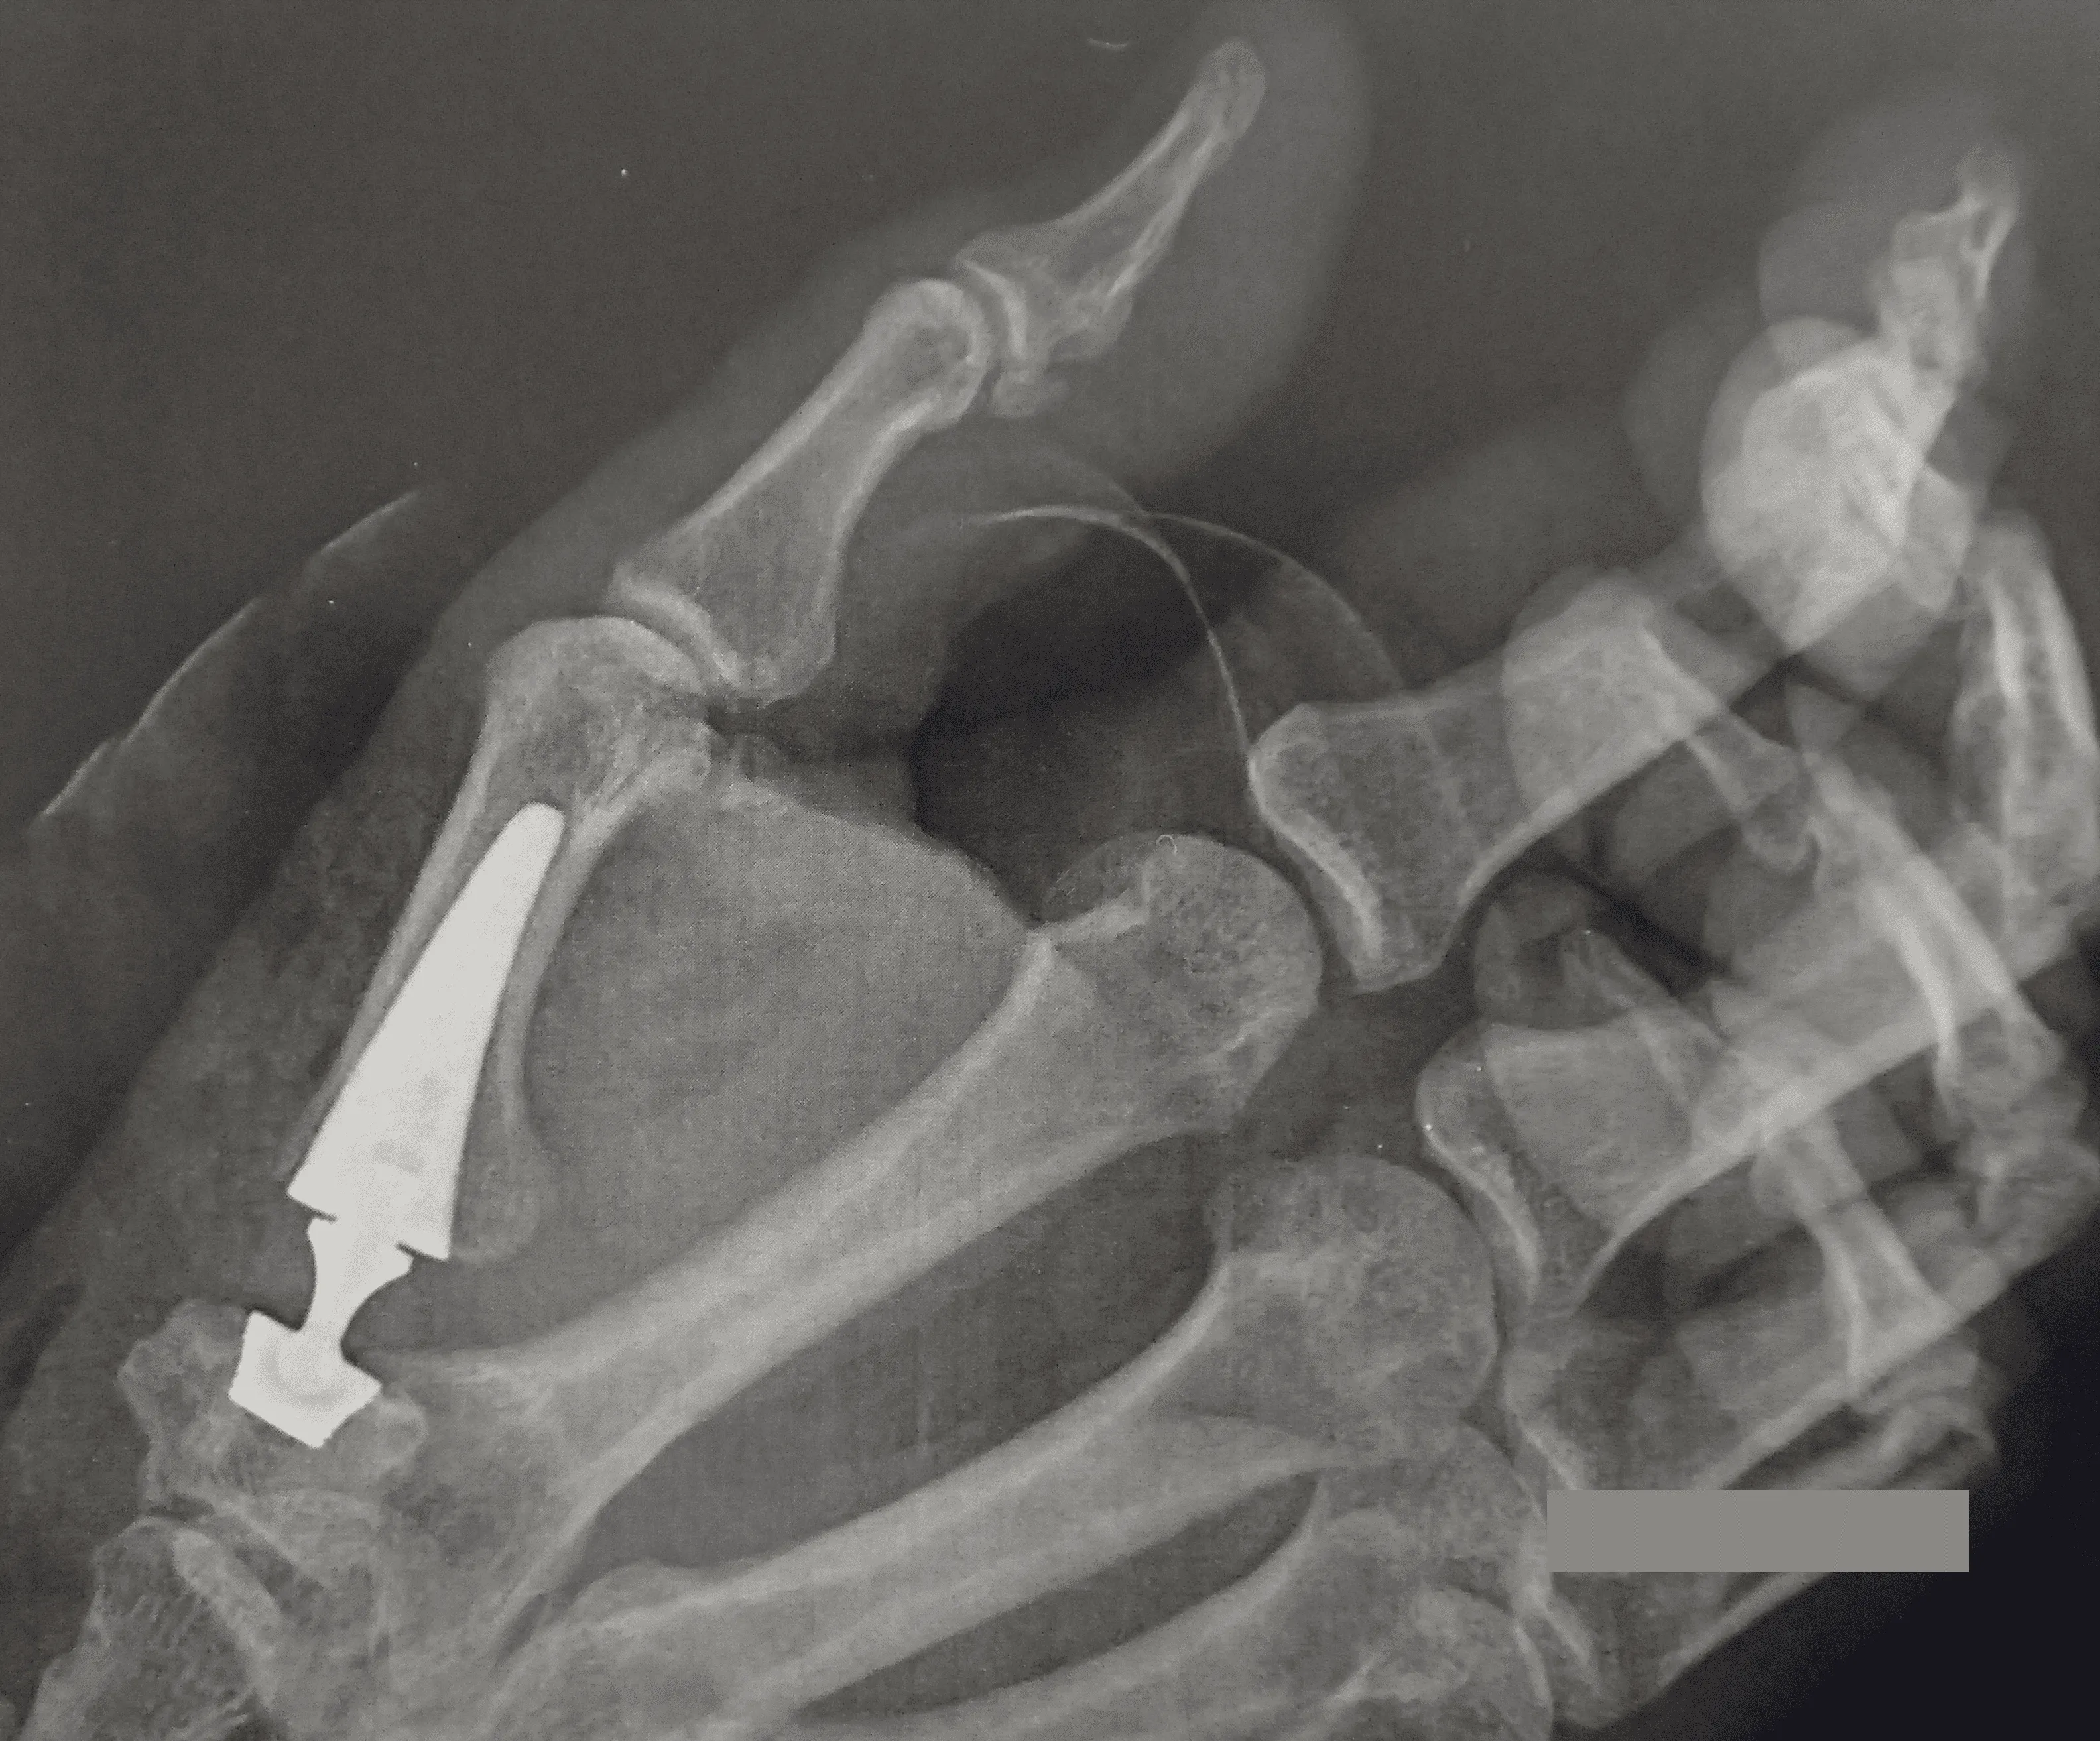

- Beeldvorming: meestal wordt een röntgenfoto gemaakt van de duimbasis. Op de foto is duimartrose te herkennen aan een versmalde gewrichtsspleet door verlies van kraakbeen en eventuele botuitsteeksels (osteofyten). Zo’n foto bevestigt de diagnose en toont de ernst van de slijtage duim. Er is niet altijd een rechtstreeks verband tussen de ernst van slijtage en de ernst van de klachten.

- Duimprothese: het versleten gewricht wordt vervangen door een kunstgewricht (duimprothese). De beweeglijkheid van de duim blijft behouden, er is een betere grijpkracht en de revalidatie verloopt relatief snel, maar een duimprothese is minder geschikt voor zeer zware belasting. Deze ingreep heeft onze voorkeur waar mogelijk gezien het snellere herstel.

- Trapeziumresectie: het trapeziumbot (een handwortelbeentje) wordt operatief verwijderd. Vervolgens plaatst de chirurg een stukje pees of kunstmateriaal op de plek van het verwijderde bot (interpositie-artroplastiek) om bot-op-bot contact te voorkomen. Deze ingreep neemt de pijn weg en behoudt enige beweeglijkheid, maar het herstel duurt enkele maanden en de maximale knijpkracht van de duim kan iets verminderen.